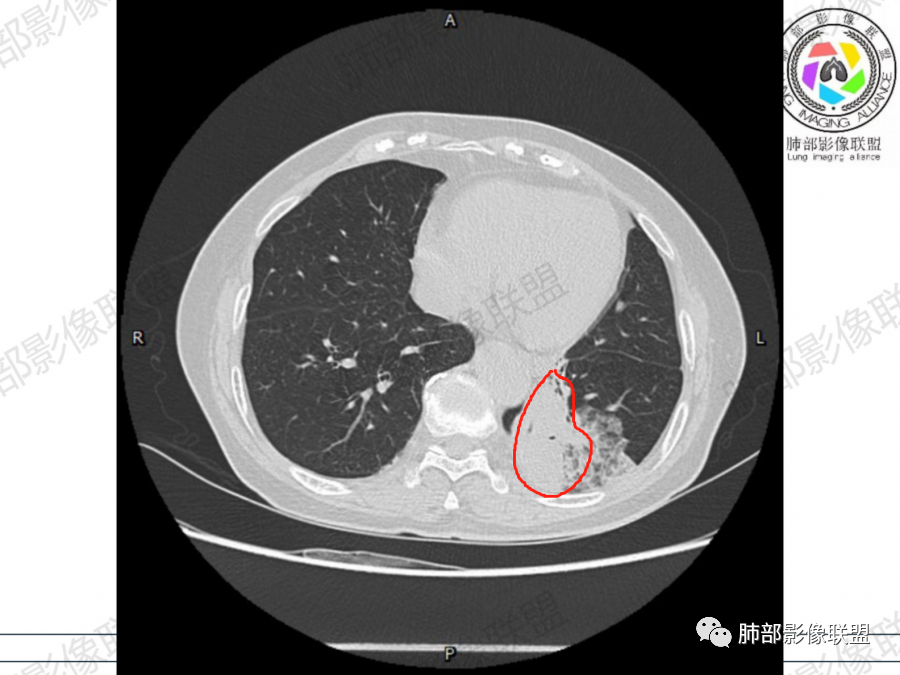

晨读病例,老年人男性 左肺下叶病灶,实性病变加上边界清晰的磨玻璃影,实性病变可见明显的膨胀性生长,增强实性部分可见血管照影征,考虑腺癌,粘液腺癌可能。

左肺下叶胸膜下混合磨玻璃影,磨玻璃边界清晰,支气管进入后堵塞,增强轻中度强化,无明显坏死空洞。

空腔+铺路石征+边界清楚GGO+病灶内血管局部扭曲+强化不均匀+病史长,指向腺癌,特别是粘液腺癌

晨读:左肺下叶胸膜下实性高密度影,部分伴有网格样增厚,内部可见小空泡,壁光滑,周围伴有磨玻璃影,边界清,近端可见支气管穿行,远端支气管堵塞,胸膜下脂肪间隙可见,病变整体收缩,部分有彭隆,增强后可见血管穿行,强化尚均匀。

左肺下叶实变及磨玻璃影,宽基底与胸膜相远,磨玻璃边界清晰,边缘膨隆,病变内近端支气管堵塞,不均匀强化,可见血管影,考虑腺癌,鉴别结核

胸CT:左下叶胸膜下大片斑片影,长轴沿胸膜分布,实变、GGO混杂,磨玻璃边界清晰,粘液密度,小叶内间隔增厚,支气管进入后堵塞(枯枝),增强轻中度强化,血管造影征。常规考虑:肺腺癌?淋巴瘤?鉴别不典型病原体感染。

周围GGO,呈碎石路征,边界清楚

主体病灶

2、影像表现:无肺气肿背景,病变定位于左肺下叶背内侧基底段,病灶呈不规则团块影,靠近胸膜侧,其内密度不均匀,内见空洞、实变及磨玻璃影,磨玻璃影呈碎石路征,边界清楚,实性肿块边界膨隆,其内见空洞。空洞周围比较实。病灶较大的支气管通畅,细小的支气管成“枯枝征”。无胸膜增厚及胸膜腔积液,增强扫描呈中度强化,见血管造影征。